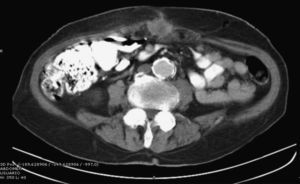

Clinical symptoms were abdominal pain of a month duration located in the mesogastrium and a weight loss of 24kg, with no vomiting or changes in bowel habit. Physical examination with palpation detected a painful, non-pulsatile mass in the umbilical region that seemed to be attached to the abdominal wall. Lab workup upon hospitalization was normal. Abdominal CT with contrast demonstrated a round lesion with a hypodense (necrotic) center in the abdominal wall of the umbilical region, with an approximate size of 3.6cm and apparent intraluminal extension (Fig. 1). MRI confirmed a tumor measuring 4cm×3.3cm×3.5cm with peritoneal involvement, but no relationship was observed with the intestinal loops. Images of satellite lesions were also detected, which were suggestive of small peritoneal tumor implants. Core needle biopsy was positive for malignant cells and suggested adenocarcinoma of intestinal origin (Fig. 2).